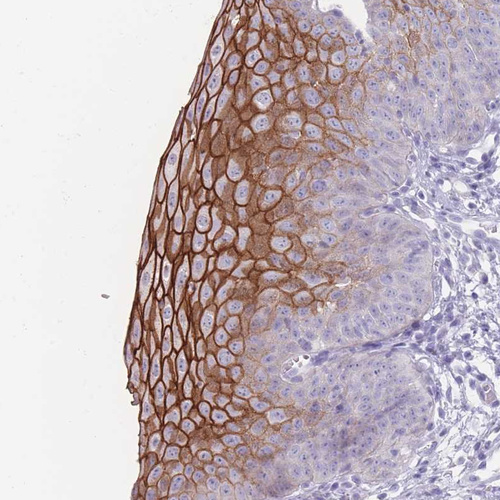

Immunohistochemical staining of human kidney shows strong membranous positivity in cells in distal tubules.